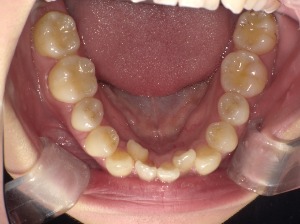

「歯並びが悪い」とは、歯が重なっていたり傾いていたりして、上下の歯がうまく噛み合っていない状態のこと。

このような状態を不正咬合といいます。

2. 「見えない場所で汚れが溜まる」虫歯・歯周病リスク

歯がデコボコしていると、歯ブラシやフロスが届かない場所が増えてしまいます。

そこに食べかすやプラークが溜まると、虫歯や歯周病の温床になります。

たとえば、歯が重なっている部分では…

- 磨き残しが増える

- 歯石がつきやすくなる

- 歯茎が腫れる・血が出る

これが慢性化すると、歯を支える骨が溶けてしまう「歯周病」に。

歯並びの悪さは、“見た目”よりも“歯の寿命”に関わる問題なのです。